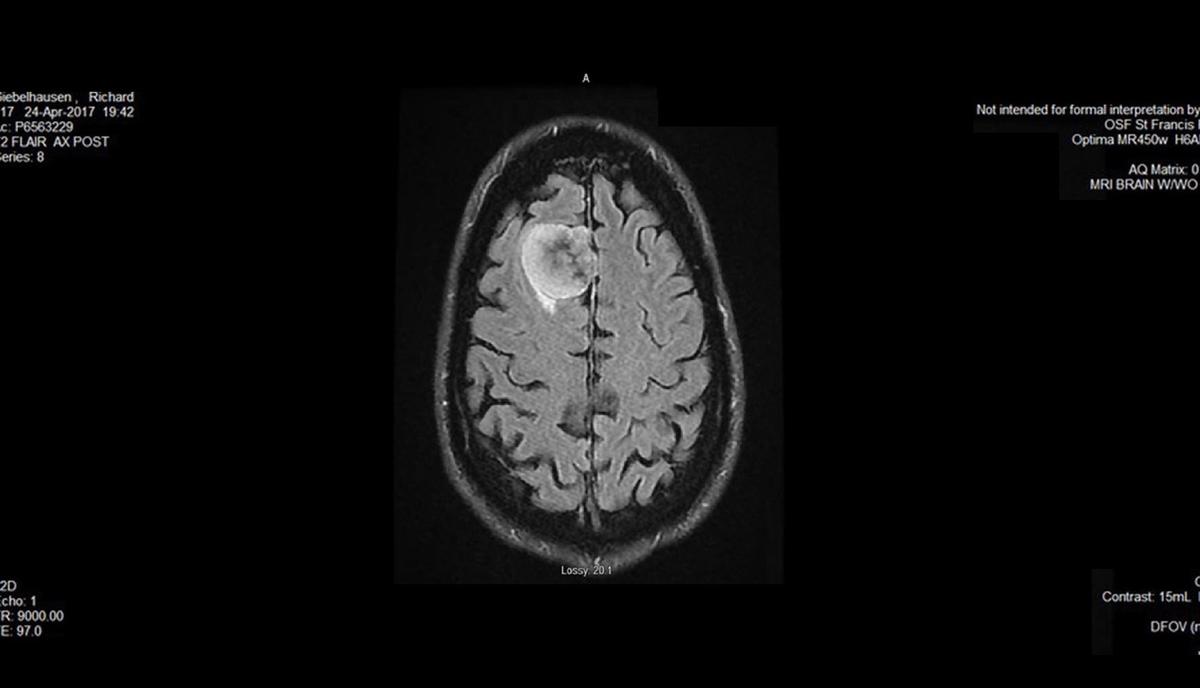

Cancer Brain Tumor Scan Image

An unexpected brain tumor, an unbelievable comeback

One man’s story from diagnosis to surgery to recovery and back to competing in triathlons.

See how determined he was for a recovery